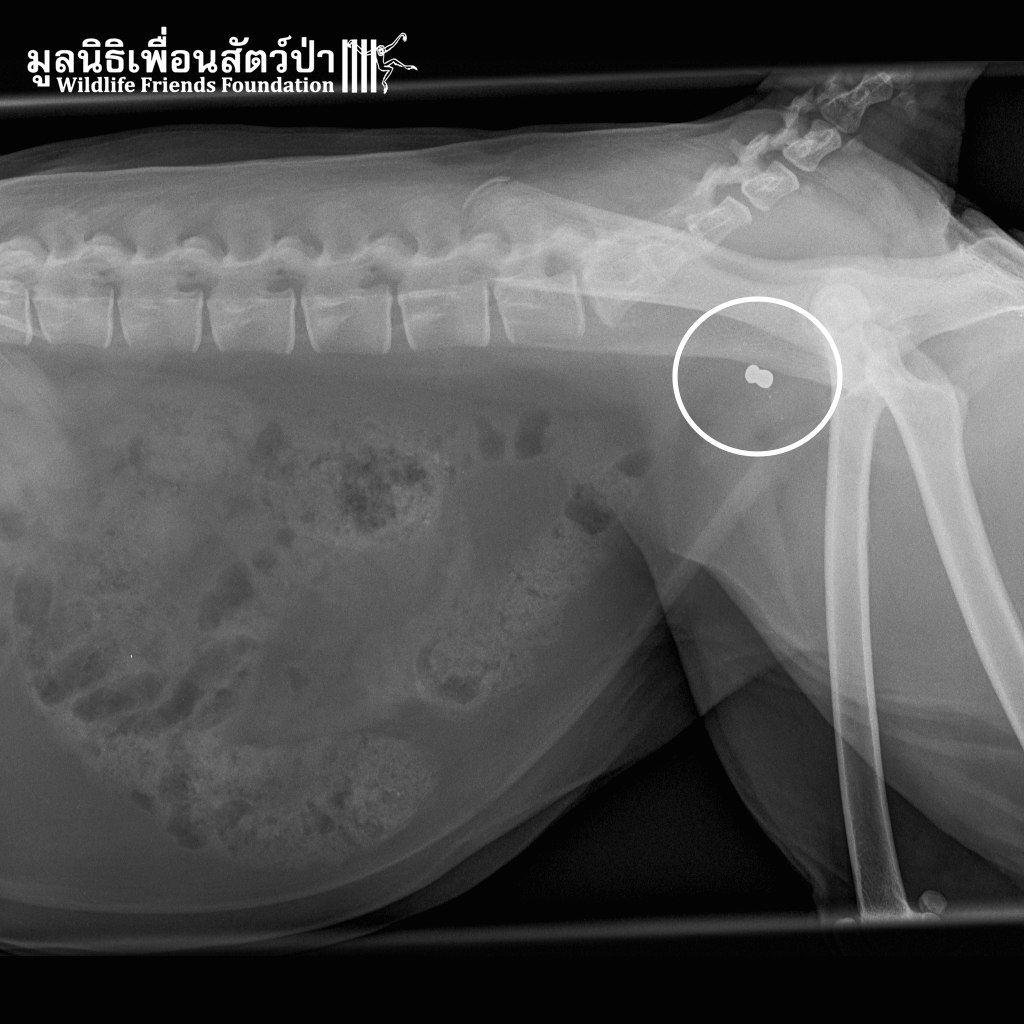

On examining this male primate it was discovered he had an infected wound, which had caused swelling of his eyelids and closure of the eyes. X-ray confirmed that he had actually been shot between the eyes. The bullet had missed both eyes and time will tell whether it has damaged the optic nerve. The X-rays also showed that Frank, as he has been named, has suffered several bullet wounds in his life. Though he had been castrated this has obviously not resolved the human-animal conflict his troop is causing.